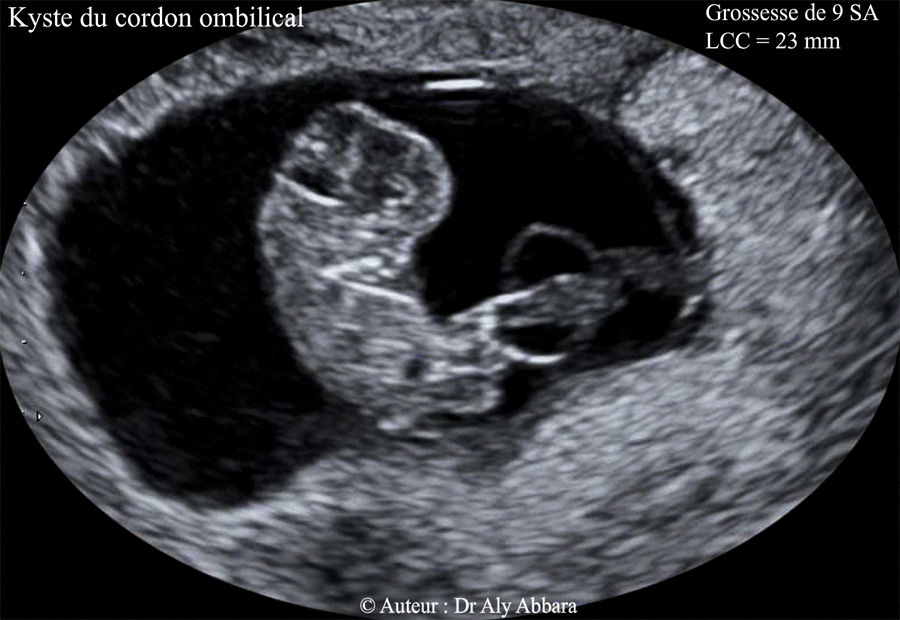

Kyste Du Cordon Ombilical Grossesse De 9 Sa